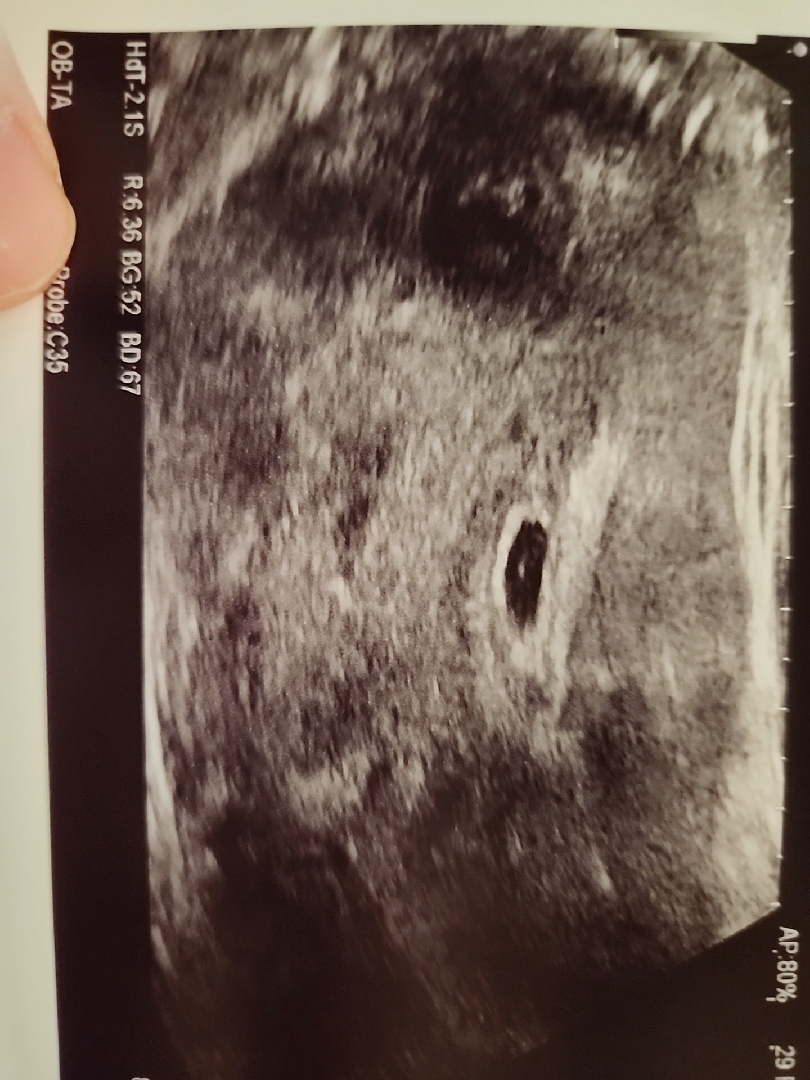

오늘 드뎌 아기집 봤네요!

다른분들처럼 똥~그랗게 예쁘진않지만 제눈엔 너무 예쁘네요ㅠ 건강하게 딱 붙어있어서 9월에 건강하게 잘 만나쟈🙏🫶